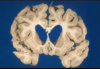

Glioblastoma multiforme

Pseudopallisading necrosis and microvascular proliferation

Ring enhancing - due to breakdown of BBB